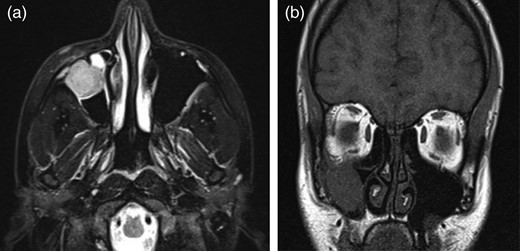

A 19-year-old female patient visited our clinic with complaints of a painless mass in the inferior eye lid of the right eye (OD). Best-corrected visual acuity was measured 10/10 with a Snellen card in both eyes. On palpation, a firm, irregular, non-reducible mass of ∼3 cm was noted in the inferior orbital rim of the OD (Fig. 1a). The mass was inseparable from the inferior orbital rim. Additionally, there was diplopia on the downward gaze and ophthalmoparesis in the OD. Fundus examination of both eyes was normal. The patient's history and general physical examination were unremarkable. A complete blood cell count and serum laboratory values were normal. Magnetic resonance imaging (MRI) revealed an extraconal solid mass measuring 3 × 3 cm in the region of the right inferior temporal orbital wall (Fig. 1b). The paranasal sinuses were normal. No definite intracranial extension was seen.

(a) A 19-year-old female patient with an immobile mass in the right inferior temporal location. (b) The MRI results of the patient show a mass fixed to the inferior orbital wall.